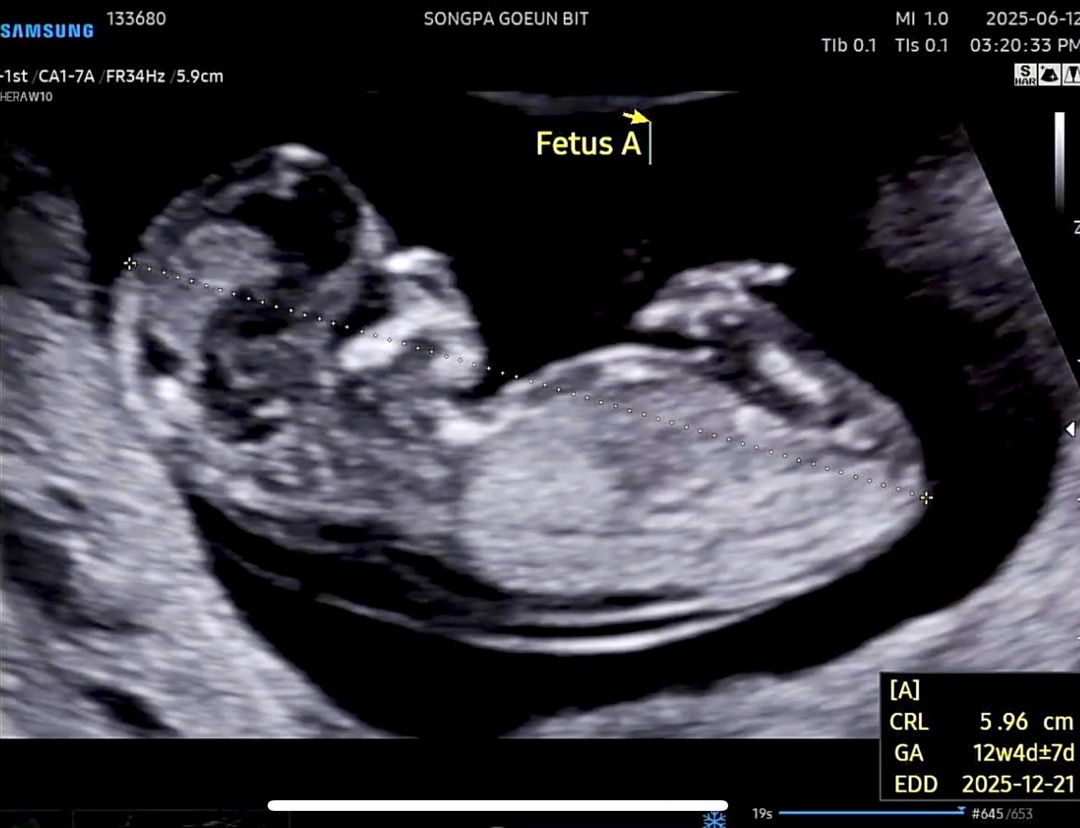

쌍둥이 12주차 각도법좀 봐주세욤😅 A

쌍둥이 오늘 12주차 초음파 보고왔네요^^; 음.. 각도법상 둘이 너무 다른느낌이긴한데.. 확인 부탁드려요🧐

돌기가 가려져서 잘 안보이네요.